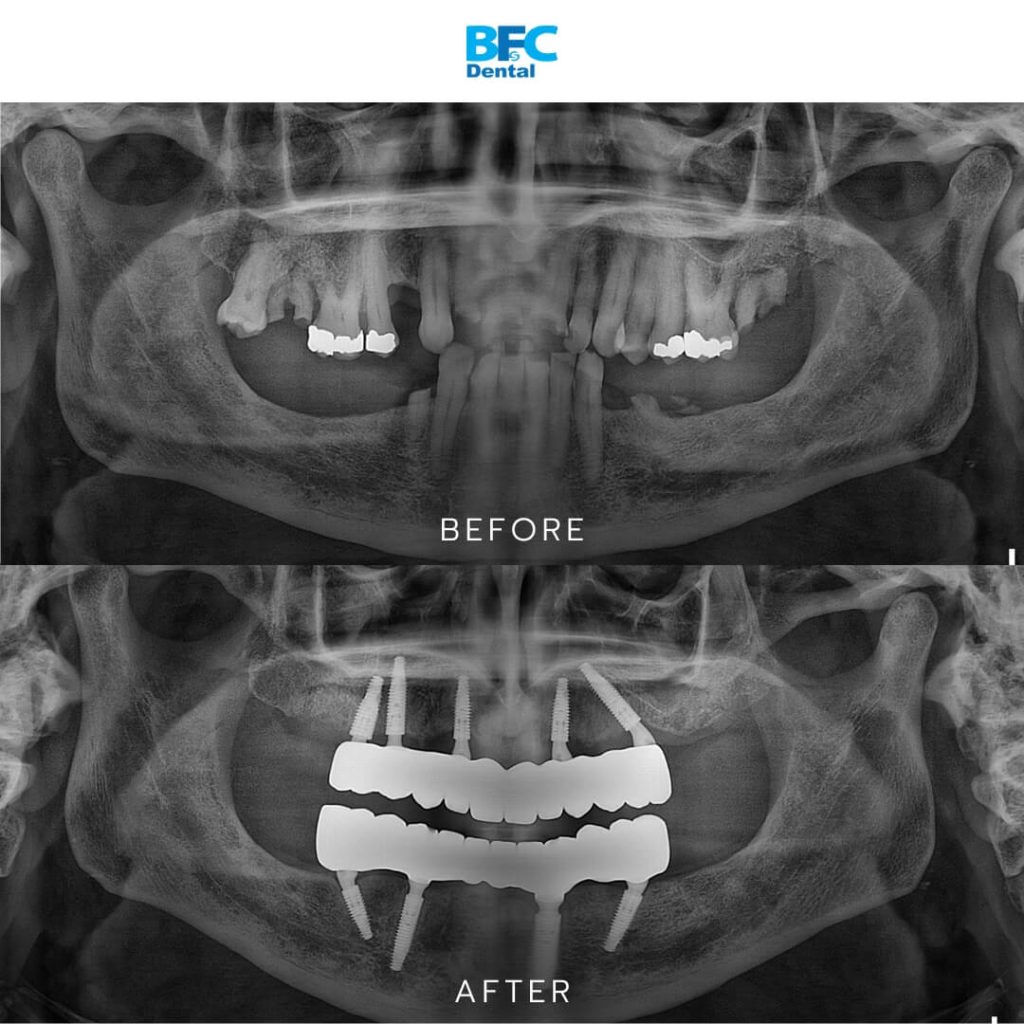

Full mouth dental implants involve placing multiple implant posts into the jawbone to support a complete arch of prosthetic teeth. One of the most recognized techniques is the All–on–4 concept, which uses just four implants per arch, though some cases may require five or six implants for optimal stability. These implants anchor a full bridge of teeth firmly to the jawbone.

The treatment plan included placing five implants in the upper jaw and four implants in the lower jaw. Within 24 hours, he received a temporary nanoceramic FP1 bridge so he could return to daily life immediately. During the first few months he followed a soft diet while the implants integrated with the bone.

After one year he returned to receive his final restoration, a full zirconia FP1 bridge. This bridge does not have a bulky pink gum portion. Instead, it provides a sleek natural look that feels comfortable and is extremely durable.